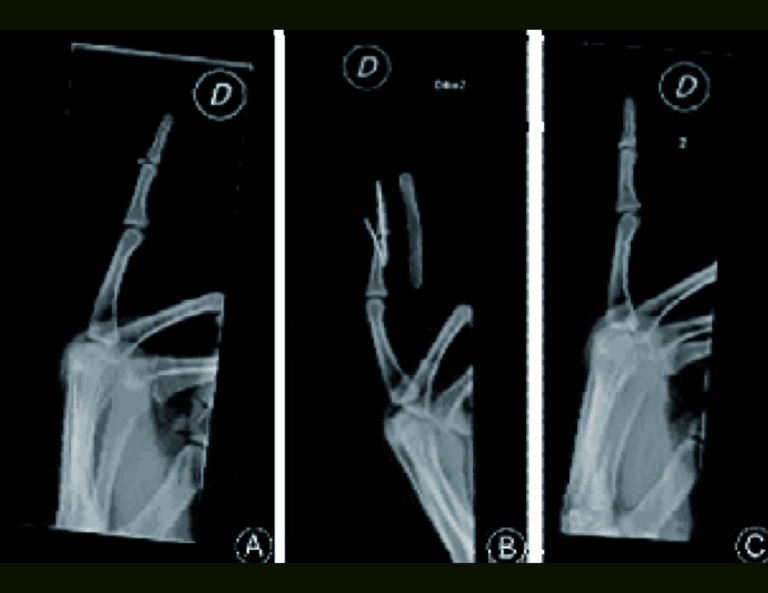

Management of mallet fractures is still a matter of discussion throughout the literature. For some authors, mallet fractures involving more than 1/3 of the articular surface and palmar subluxation of the distal phalanx require surgical treatment. In this study we retrospectively compared three different techniques for mallet fractures: Kirschner wire fixation with extension block pinning of the distal interphalangeal joint (EBP), Kirschner wires used as joysticks (KWJ) and interfragmentary mini-screws for open reduction and internal fixation (ORIF).